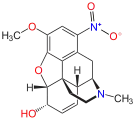

Nitrogen morphine derivatives

- 1-Nitrocodeine cas?

- Codeine-N-oxide

- Morphine-N-oxide

Structures

| Morphides | ||||

|---|---|---|---|---|

1-Nitrocodeine 1-Nitrocodeine |

Codeine-N-oxide Codeine-N-oxide |

Morphine-N-oxide Morphine-N-oxide | ||